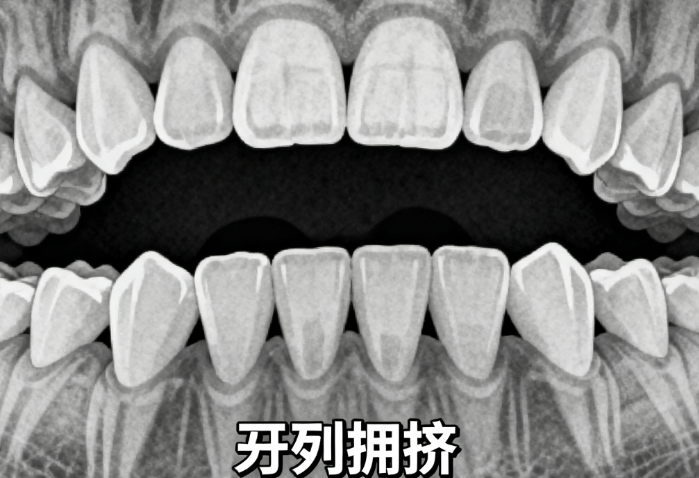

東莞口腔醫(yī)院正畸科全方面引入3D口掃、AI智能方案設(shè)計(jì)、數(shù)字化模擬預(yù)測(cè)系統(tǒng),可在治療前穩(wěn)準(zhǔn)預(yù)演矯正全過程及較終療效。無論是骨性齙牙、地包天、深覆合還是牙列擁擠,都能制定個(gè)性化方案,確?!耙淮纬C正,終身受益”。

小林因牙列擁擠、前牙扭轉(zhuǎn)較重,長期不敢大笑。經(jīng)袁東輝醫(yī)生評(píng)估后,選擇傳統(tǒng)金屬托槽矯正,總費(fèi)用僅5200元(含保持器)。18個(gè)月后,牙齒整齊如新,面試時(shí)自信展現(xiàn)笑容,順利拿到心儀offer。